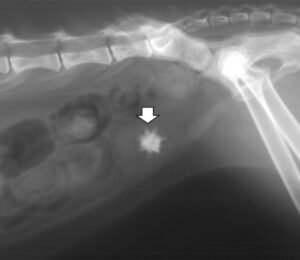

რა არის კატების შარდკენჭოვანი დაავადება? როგორ ავიცილოთ ის თავიდან? როდის მივმართოთ სასწრაფოდ ექიმს?